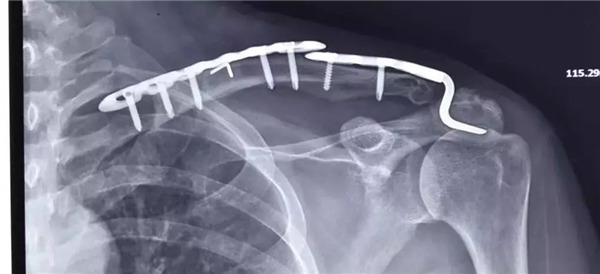

傳統(tǒng)手術(shù)方式——大切口上鋼板